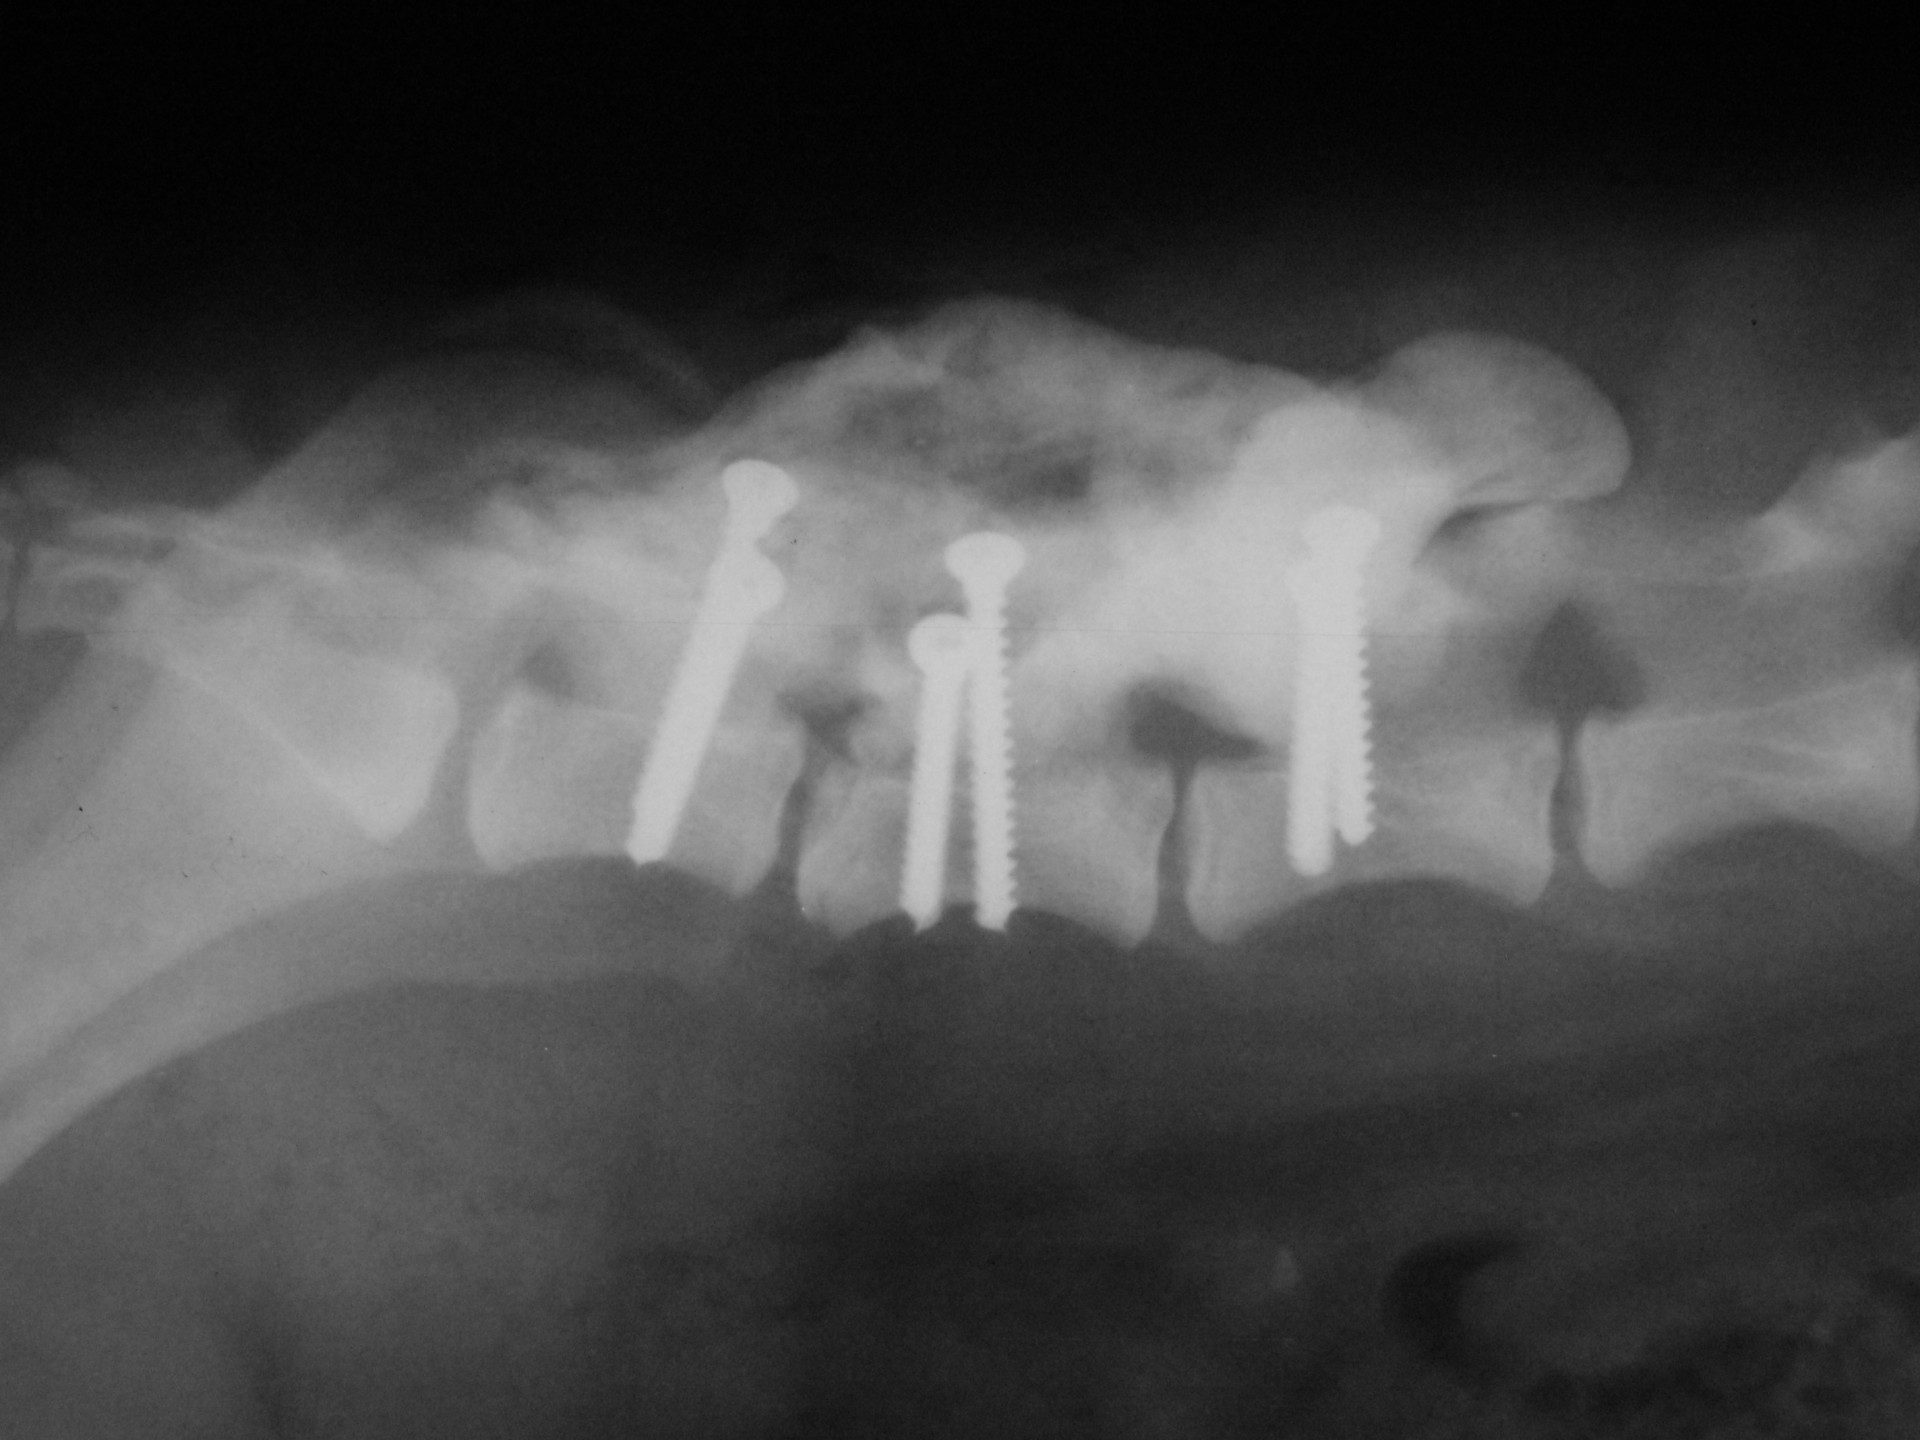

A törött csigolyatestek adaptációja és rögzítése a nyitott gerinccsatorna mellett komoly kihívást jelent. A későbbi elmozdulás elkerülésére többféle műtéttechnika alkalmazható, melyek közül a csigolyatestek lemezes osteosynthesise ill a fixateur interna használata terjedt el leginkább. Első esetben a sérülés előtti és mögötti csigolyákat lemez és csavarok segítségével egymáshoz rögzítjük, míg az utóbbi esetben a törés előtti és mögötti egy vagy több csigolyatestet két oldalról behelyezett csavarok és egy steril kétkomponensű akrilát műgyanta segítségével rögzítjük.

Szerencsés esetben az állat a műtétet követően néhány héten belül, akár tünetmentesen gyógyul. Az implantátumok későbbi eltávolítására - amennyiben szövődmény nem alakul ki - általában nincs szükség.

Bármilyen műtét után kialakulhat olyan szövődmény, mely gennykeltő baktériumok műtéti sebben történő elszaporodásával jár (szeptikus szövődmény). Különösen igaz ez olyan beavatkozásokra, amikor valamilyen idegen anyag (implantatum) kerül a szervezetbe beültetésre. Ilyen idegen anyag a gerinctörés műtéteknél használatos fixateur interna rögzítőanyaga (akrilát műgyanta) is. Abban az esetben, amikor a szeptikus szövődmény antibiotikumok célzott adásával nem gyógyítható, a test számára idegen anyagot el kell távolítanunk. A gerinctörés műtéténél ez a nyitott gerinccsatorna miatt fokozott kockázatot jelent. Az implantatum eltávolítását követően azonban a szeptikus folyamat gyógyul és a helyén kialakuló kötőszövet a fixateur externának megfelelően rögzíti a gyógyulófélben lévő csigolyát is.